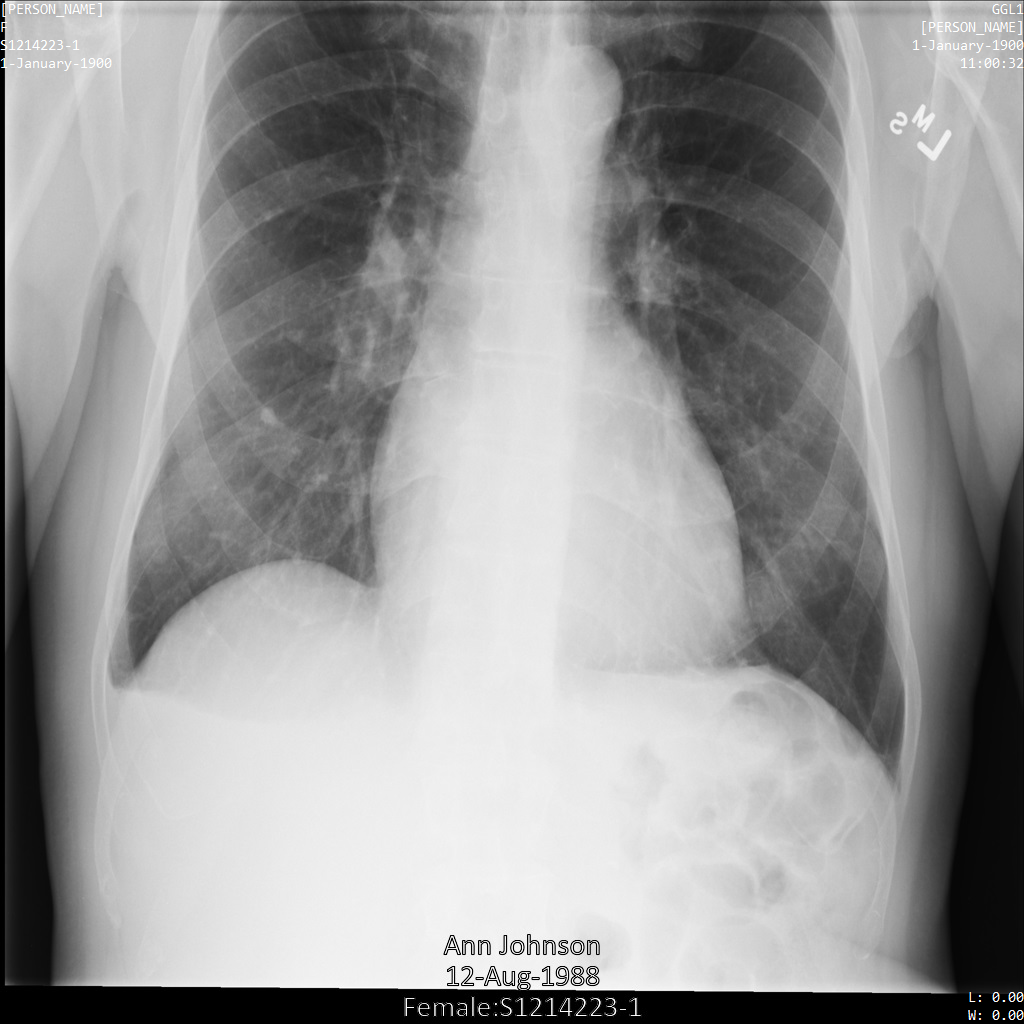

En cada una de las siguientes secciones, se proporcionan ejemplos de cómo desidentificar datos de DICOM mediante varios métodos. Se proporciona un resultado de la imagen desidentificada en cada muestra. En cada muestra, se usa la siguiente imagen original como su entrada:

Puedes comparar la imagen de salida de cada operación de desidentificación con esta imagen original para ver los efectos de la operación.

En la siguiente imagen, se muestra una radiografía sin ocultamiento de un paciente: